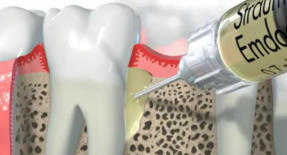

Eine erfolgreiche anerkannte Methode stellt die Behandlung mit Schmelzmatrixproteinen (Emdogain - Firma Straumann) dar.